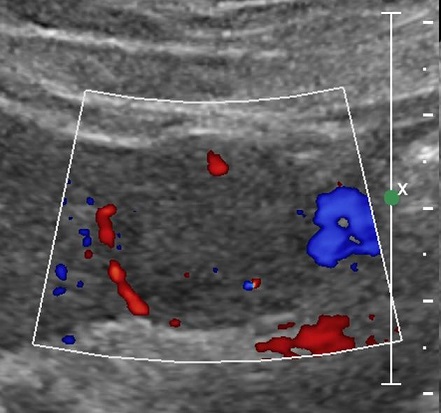

Image echographique du

carcinome hepatocellulaire : Aspect lesionaire du HCC

est une masse hyperechogene , hypoechogene ou mixte , unique

ou multiple a contour net irregulier ou mal de definissable

. Au debut , le forme plus souvent est un infiltrant a

isoechogene ,et puis sous forme nodulaire de petite

taille est hypoechogene et si en forme nodulaire de grand

taille c'est hyperechogen avec des zones necrotiques

hypoechogenes . Le " Rim sign " ou signe de "Bending sign "

le plus souvent en voyait dans HCC , ce qui en n'a pas presente

dans abces du foie . De HCC a grand taille , aspect

echographique est un masse hyperechogene multinodulaire a

contour maldefinie avec centre necrotique hypoechogene de

contenant des bougeons . Image echogaphique de thrombus de

veine porte